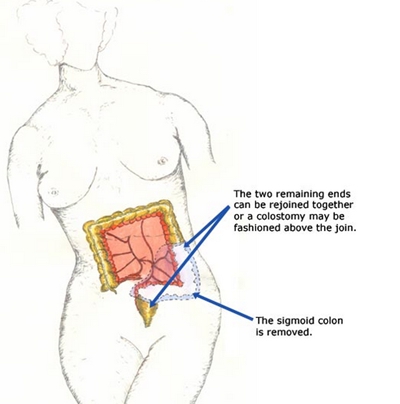

A:盲腸炎症狀最多見是肚臍周圍或者右下腹疼痛,右下腹局部按壓會出現疼痛,還有部分患者會出現食慾差,噁心,嘔吐,輕度發熱等可能性,一般需要行回盲部B超檢查,查血常規明確疾病診斷。早期可以採取非手術治療,腸道休息,胃腸減壓,可以腸外靜脈營養支持,使……

A:盲腸炎在醫學上稱為闌尾炎,它是最常見的普通外科疾病。它可以分為急性闌尾炎和慢性的闌尾炎,急性闌尾炎的症狀是轉移性右下腹痛,發燒,疼痛持續,比較劇烈。一旦發生急性闌尾炎,可以考慮藥物治療,氧氟沙星和奧硝唑輸液治療,也可以直接採用手術治療;慢性……

A:盲腸炎也稱闌尾炎,它是由於回盲部炎症導致的消化系統疾病,臨床上最多見為噁心嘔吐,腹痛,腹脹。以右下腹為疼痛為主,麥氏點壓痛,早期可以通過查體及血常規,腹部B超檢查,消化道鋇灌腸能夠明確疾病診斷。輕者可以應用廣譜抗炎藥物治療,如注射用頭孢西丁……

A:慢性盲腸炎也就慢性闌尾炎,它是由於回盲部闌尾發炎而引起的消化系統疾病,臨床主要症狀為右下腹間歇性疼痛,噁心,嘔吐,以麥氏點疼痛為主,局部按壓有疼痛,可以用B超或者消化道鋇灌腸能夠確診。可以用抗炎藥物對症處理,一般容易反覆發作。如果慢性闌尾炎……

A:兒童盲腸炎的症狀也稱為兒童闌尾炎,它是由於回盲部感染原因導致的消化系統疾病,一般臨床上最多見為噁心,嘔吐,右下腹疼痛,以麥氏點為著,查體:可見麥氏點壓痛,嚴重時會出現腹反跳痛,腹膜炎體徵等,需要行血常規,B超檢查,如果診斷明確時,建議行腹腔……

A:盲腸炎也稱為闌尾炎,它是指盲腸末端闌尾發炎而引起的消化系統疾病,早期可以口服廣譜抗生素如鹽酸左氧氟沙星膠囊,甲硝唑片等,如果闌尾炎穿孔,體溫可升至39度,並且還有腹膜炎可能性。可以行血常規,腹部B超檢查及查體等確診。確診需要立即手術,術後可……

A:盲腸炎,也就是闌尾炎。闌尾是自大腸初段長出的管狀器官,分為急性闌尾炎和慢性闌尾炎,急性闌尾炎因為起病比較急驟,所以需要手術治療。闌尾炎的症狀特徵主要就是腹痛、噁心和嘔吐。腹痛多是由上腹部開始,以腹脹、悶痛為主,逐漸向右下腹轉移。患者可能伴有……